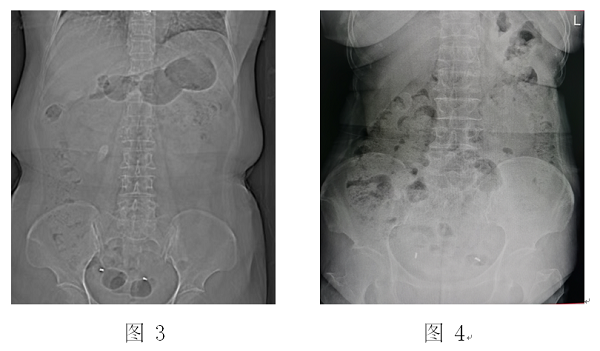

泌尿外科主任刘伟医生认真阅片,分析病情,并经过科室讨论,建议患者采用“无管化”经皮肾镜碎石取石术治疗。经过术前准备,在麻醉医师与手术室护士的通力配合下,顺利完成“无管化”经皮肾镜碎石取石术。术后患者恢复良好,复查腹部平片未见结石残留,已顺利出院。患者及家属非常满意(见图3-图6)。